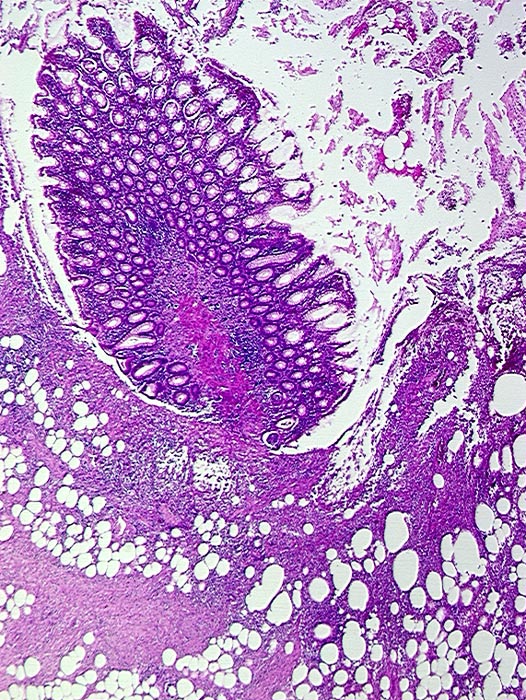

PathoPic ID 625 - Divertikulitis

Divertikulitis

Entzündung infektiös

Kolon Sigma

Darm, Anus

Partiell entzündlich zerstörtes Divertikel mit erhaltener Schleimhautinsel.

Histologie